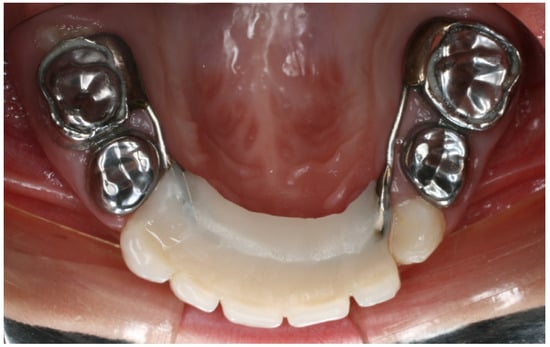

2.2. Treatment Protocol